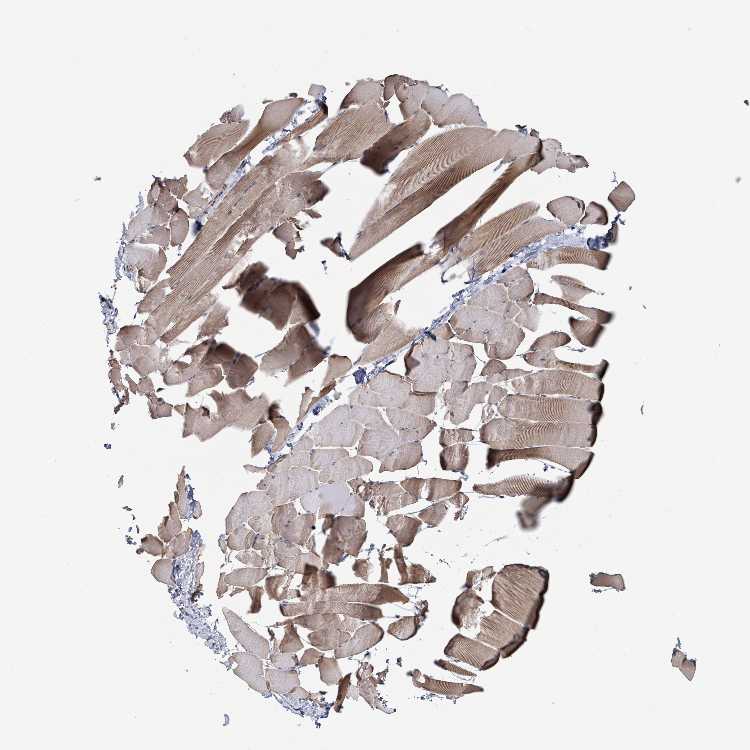

SKELETAL MUSCLE - Antibody stainingi

Antibody staining in the annotated cell types in the current human tissue is reported as not detected, low, medium, or high, based on conventional immunohistochemistry profiling in selected tissues. This score is based on the combination of the staining intensity and fraction of stained cells.

Each image is clickable and will lead to virtual microscopy that enables deeper exploration of all samples and also displays staining intensity scores, fraction scores and subcellular localization as well as patient and tissue information for each sample.

Antibody HPA050724

Myocytes Medium